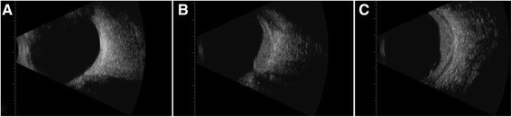

- B-scan: high internal reflectivity (흑색종과 대비)